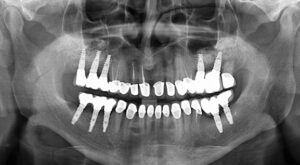

Full-Mouth Dental Implant Solutions in Rajkot

If you’ve lost most or all of your teeth, our full-mouth dental implant solutions in Rajkot can give you back a strong, beautiful smile.

- All-on-4 and All-on-6 implants

- Full-arch fixed hybrid dentures

- Zygomatic implants (for patients with low bone volume)

Every plan is customized based on jawbone analysis, ensuring comfort and durability

- Advanced Technology – OPG X-ray, computer-guided surgery, 3D Intra Oral Scanner and painless dentistry ensure precise and comfortable treatment.